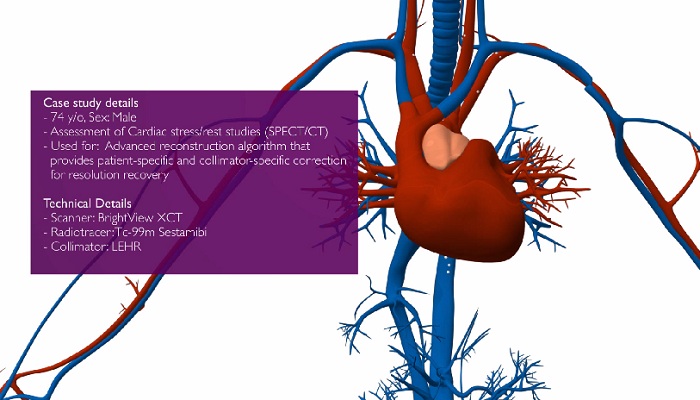

""لطالما كان التشخيص الموثوق هو الهدف الذي تسعى إليه دائمًا. وبسبب نظم السداد المستندة إلى القيمة اليوم والحاجة إلى نتائج سريرية محسّنة، أصبح التشخيص بشكل متزايد ضرورة لا مفرّ منها. بالتالي، يجب على كل خطوة من خطوات العملية التشخيصية أن تراعي الأمرين معًا وتوفر نتائج عملية فائقة الجودة. لمساعدتك في تحقيق ذلك، نحن نقدم لك: يمكنك معرفة كيف تستطيع حلول الأشعة التي نقدمها مساعدتك في الوصول إلى التشخيصات السريرية بفعالية وثقة.

"باستخدام تقنيات التصوير المتقدمة من Philips مثل التصوير ثلاثي الأبعاد وعرض الشدة القصوى (MIP) وإعادة التشكيل متعدد الأسطح (MPR)، يمكننا الحصول على الصور بسهولة ومعالجتها لتحسين تشخيصنا. نحن نأخذ فكرة أفضل عن المستوى الذي وصل إليه المرض، كما يمكننا تقديم نصائح أفضل إلى الطبيب السريري حول ما يحدث." دكتور دارسي ليتل